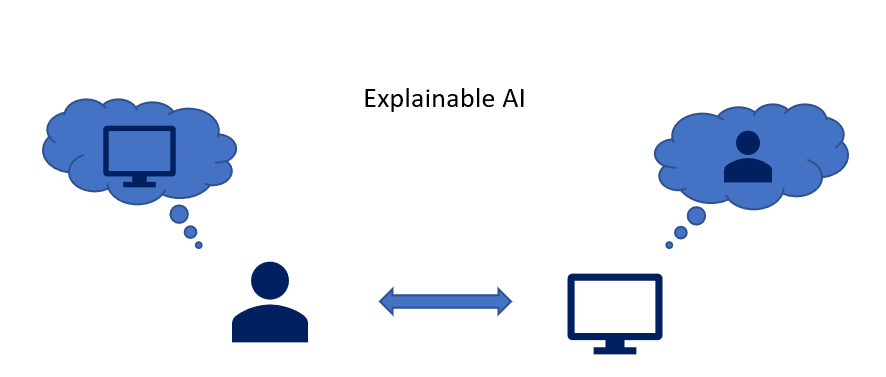

特征选择

特征工程是提高任何算法的预测能力的另一个关键步骤,并且可以提高模型的清晰度。由于拥有大量可用数据,因此必须谨慎选择功能,这不仅需要确保模型性能,而且还要确保模型的可解释性。如果忽略或错误处理了特征选择,则在不同模型类型之间可能会发生许多陷阱。例如,数据泄漏是一个问题,当包含取决于您的预测变量的功能或在预测时否则无法使用的功能时,将导致性能指标膨胀,最终导致模型无用,而与模型类型无关。此外,从DL模型中提取特征(涉及将最后一层的值用作特征)已成为图像分析中广泛使用的技术。尽管这种方法可以产生大量的信息功能,并为模型准确性带来有利的结果,但除非进行了适当的尽职调查,否则通常不清楚这些功能代表什么。如果不强调创建可解释的工具,那么其中许多因素很容易被忽略。

通常根据特征对预测能力的影响来选择特征,这种方法可能会忽略其他关键特征,例如现场的先验知识和数据可访问性。很多时候,在创建/测试预测模型的过程中进行特征选择会确认以前已知的关联,例如BRCA1预测会发展为乳腺癌或卵巢癌。但是,当评估大型数据集时,即使经过实验验证的关联也可能被数据的整体噪声淹没。因此,整合专家知识的努力可以确保预测是由潜在的生物学机制驱动的,从而使该模型不仅更具解释性,而且更加可靠。最近,Javanovic等通过结合使用传统选择技术和领域知识发现的特征,利用Tree Lasso正则化模型来预测小儿再入院。他们发现,与使用传统的套索模型相比,此结果模型更易于解释,而性能没有明显损失。这凸显了一个事实,即可解释性不需要与预测能力的权衡取舍。但是,应该指出的是,完全或过于依赖专家知识可能会加剧已知的系统偏见并限制科学发现。因此,对特征重要性的详尽搜索对于确保完整的模型透明度和生物学理解至关重要。